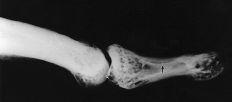

En los casos en los que la tumoración tenía un comportamiento expansivo o estaba próxima a una articulación IF se practicaron estudios radiológicos simples o de alta definición. Se constató, además de un aumento de partes blandas, una erosión ósea cortical con un ribete escleroso, especialmente en los tumores de mayor tamaño o en zonas de reducida capacidad de expansión. Las imágenes de RM mostraron patrones de intensidad variable dependiendo de la nodulación del tumor y de sus depósitos de hemosiderina (Fig. 1).

En cuanto a su sintomatología, los TCG comienzan a doler en relación con su aumento de volumen. Se comportan con agresividad local, invadiendo los compartimentos vecinos e incluso erosionando el hueso subyacente.2,5,6,9,13,15,17,29,33,37Cuando no son nodulares o claramente superficiales, es de utilidad la radiología convencional y de alta definición, en donde se aprecia un aumento de volumen y densidad de las partes blandas en la mitad de los casos y una erosión ósea con ribete escleroso en el 20% de los casos.2-5,6,9,13,15,17,37 En los estudios de RM es característica una imagen de tumoración nodular debido a los depósitos de hemosiderina, adyacente al tendón o cápsula, con áreas de disminución de intensidad de señal en T1 y T2 y otras zonas de señal isointensa al músculo en T1 e inferior a la grasa, pero superior al músculo en T2 (Fig. 1).17,29

Figura 1. Tumor de células gigantes que afectaba de forma difusa al dedo anular. Corte coronal de RM potenciada en T1 en la que se aprecian cuatro nódulos tumoreales volares que infiltran el canal digital.